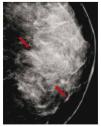

El carcinoma ductal in situ (CDIS), se presenta comúnmente con microcalcificaciones agrupadas en el 62% a 72%9 (figs. 2A-D) y gracias a esta tecnología su frecuencia relativa ha aumentado en los últimos años, así como la detección de lesiones precursoras o limítrofes como la hiperplasia ductal con atipia (fig. 3).

Figura 2 A), B) y C) Paciente de 48 años, asintomática, calcificaciones agrupadas polimorfas con distribución segmentaria CSED (flechas). D) ultrasonido, tumoración mixta, BIRADS 5: cáncer ductal in situ de alto grado.

Figura 3 Asintomática, paciente de 41 años con grupos de microcalcificaciones polimorfas izquierdas de distribución lineal (flechas), BIRADS 4C: hiperplasia ductal con atipia.